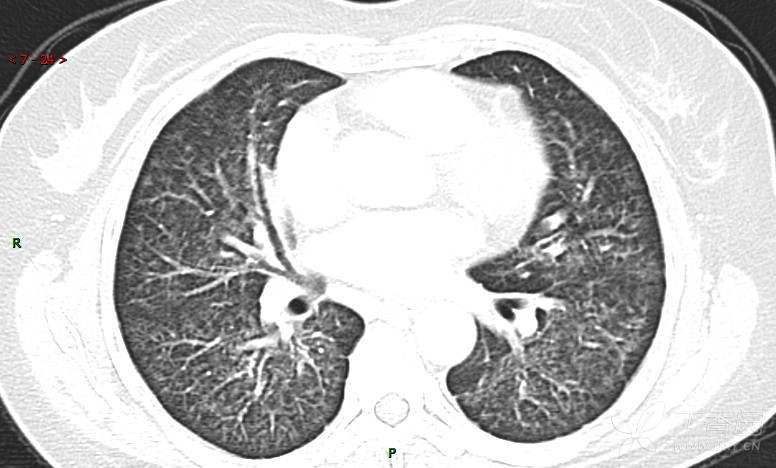

肺内弥漫性网状结节影,PET-CT却无阳性病灶,这是?(附其他2例链接)

女性,58岁,阵发性咳嗽2月,加重1月。

患者于2月前无明显诱因出现咳嗽,以阵发性干咳为主,接触冷空气后咳嗽明显,偶咳少量白色泡沫样痰,咳嗽剧烈时感憋喘,无发热、盗汗,无头痛、头晕,无胸痛、咯血,无恶心、呕吐,无腹痛、腹泻,无尿频、尿痛等不适,于当地医院给予肌注及静脉药物治疗,具体药物名称不详,效果欠佳,近1月来患者咳嗽频率较前增加,咳嗽剧烈时感双侧季肋区疼痛不适,10余天前出现发热,体温在38℃左右,伴畏寒、寒战,无头痛、头晕,无纳差、乏力等不适,药物治疗后体温降至正常,仍阵发性咳嗽,今为求进一步诊治,就诊于我院急诊,因呼吸内科暂无床位,急诊门诊以“肺间质病变”收入急诊留观室,给予“抗感染、止咳”等对症支持治疗后,今日以“肺间质性病变”收入我科,患者自本次发病以来,神志清,精神可,饮食尚可,睡眠一般,大小便正常,体重较前无明显变化。

患者活检肺组织后行PET/CT检查